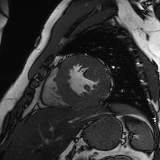

Refer to caption

Figure 2: Examples of tracking results using the proposed method (MPN-C). From left column to right: ED frame, ES frame, warped frame from ED, overlay of ES frame and the warped mask, and estimated motion field using HSV color coding. The color coding wheel legend indicates the motion directions.